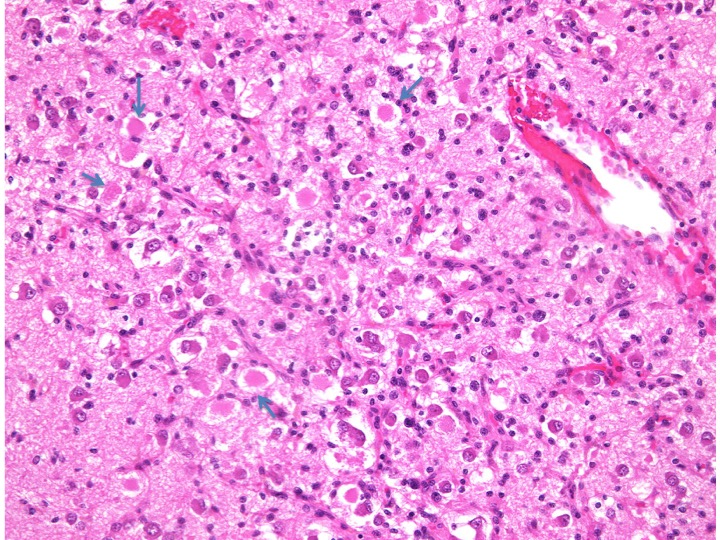

数年の経過でわずかな増大傾向を示したので全摘出しました。交通事故に遭って偶然発見された病変で、traumatic injuryが腫瘍浸潤で脆弱となったaxonに影響をおよびした可能性が示唆されます。

diffuse astrocytomaの大脳皮質浸潤で多数のhomogenous pinc bodyが見られます (arrows)。この小体は神経病理ではspheroidと呼ばれていますが、traumatic axonal injuryで見られるaxonal retraction bulb (ball) に相当するものです。通常では稀な小体ですが、本例で多数見られました。

GFAP染色でastrocyteは陽性に染まるが、axonal retraction bulbは陰性です。GFAP x200

Axonal retraction bulbはsynaptophysinに陽性に染まります。Synaptophysin x200

MIB-1 indexは低値で、2%程度です。MIB-1 x200